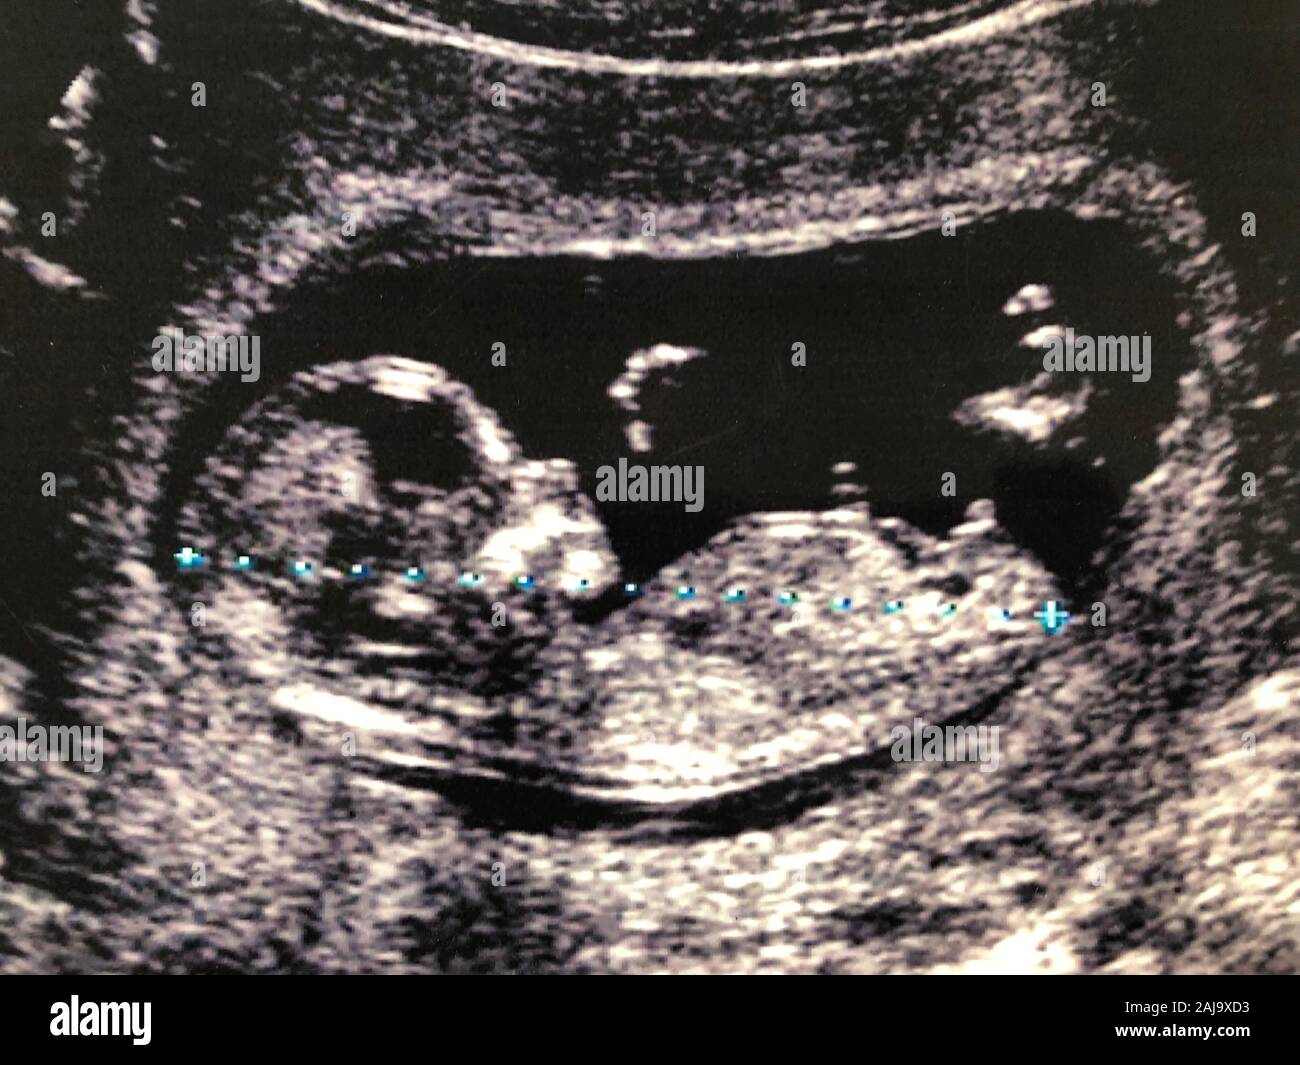

What Does Fetus Ultrasound Mean . During a fetal ultrasound, a device called a transducer is placed on the pregnant person's belly. Technicians will measure the size of the fetus at each ultrasound as they grow to look for abnormalities and possible chromosomal markers that indicate down syndrome. Fetal biometry is a test that measures the size of a fetus during pregnancy using ultrasound. It creates an image of the baby in the mother's womb (uterus). Or in some cases, it may be. This biparietal diameter calculator will take your baby's fetal measurements and show you if your baby is growing at a healthy rate based on fetal. It’s a safe way to check the. During this ultrasound, your pregnancy care provider can see your baby’s sex (if your baby is in a good position for viewing their genitals),. Fetal ultrasound is a test used during pregnancy. On a pregnancy ultrasound, the baby will look grey or white and will be located within the amniotic fluid (the dark area inside of the womb).

It creates an image of the baby in the mother's womb (uterus). It’s a safe way to check the. During this ultrasound, your pregnancy care provider can see your baby’s sex (if your baby is in a good position for viewing their genitals),. Fetal ultrasound is a test used during pregnancy. On a pregnancy ultrasound, the baby will look grey or white and will be located within the amniotic fluid (the dark area inside of the womb). Technicians will measure the size of the fetus at each ultrasound as they grow to look for abnormalities and possible chromosomal markers that indicate down syndrome. This biparietal diameter calculator will take your baby's fetal measurements and show you if your baby is growing at a healthy rate based on fetal. Or in some cases, it may be. Fetal biometry is a test that measures the size of a fetus during pregnancy using ultrasound. During a fetal ultrasound, a device called a transducer is placed on the pregnant person's belly.